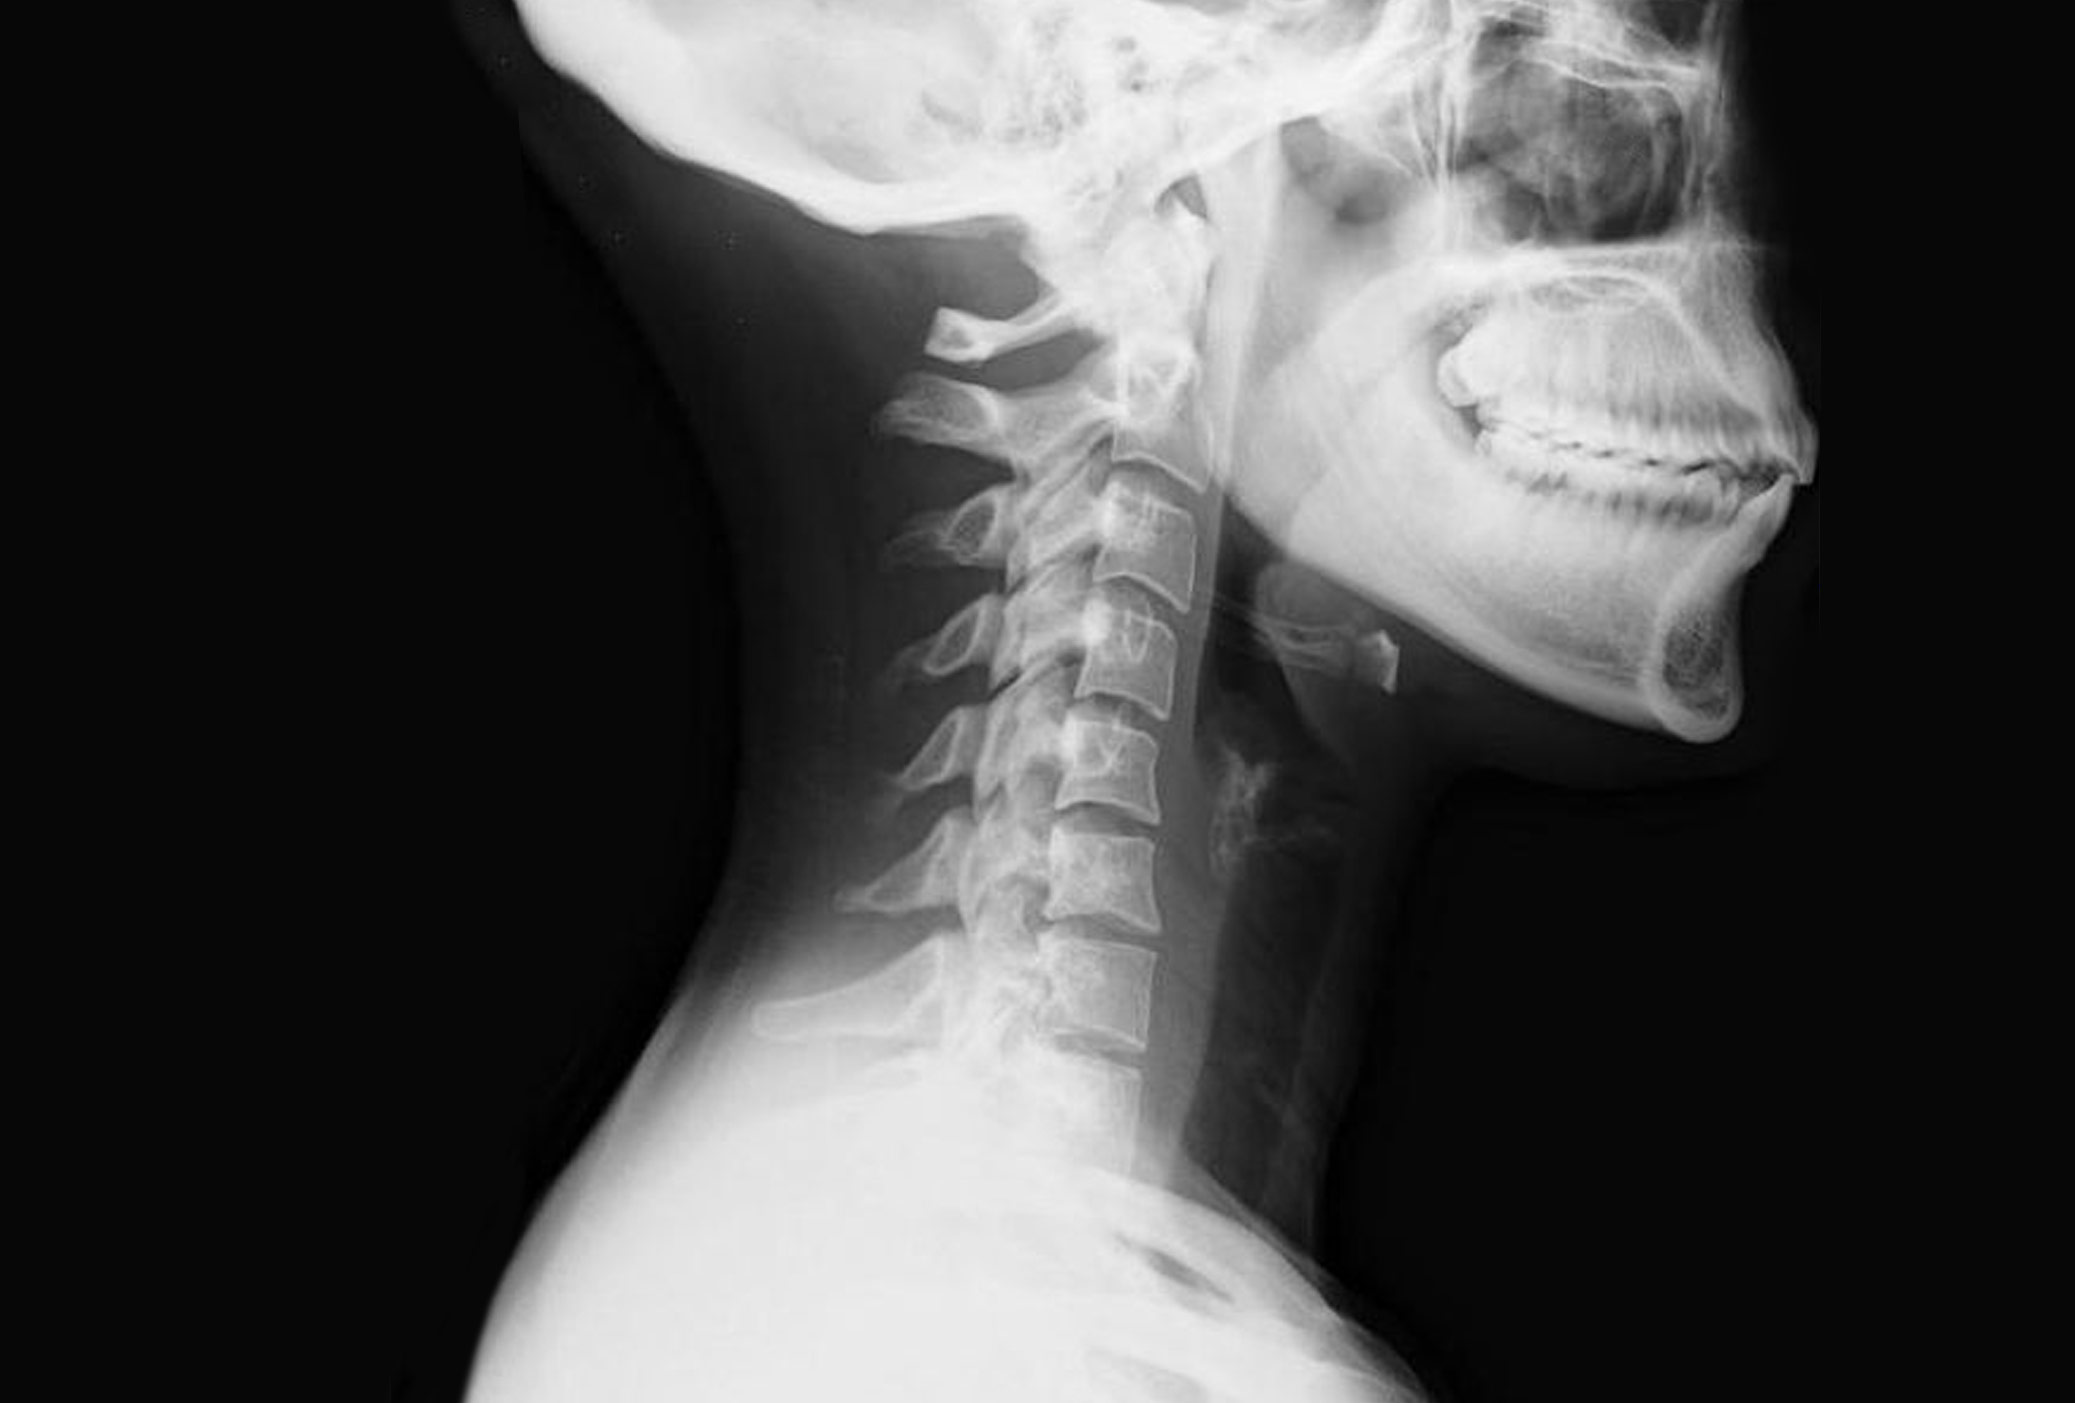

Latigazo Cervical Tiempo De Baja. WebTiempo de baja por latigazo cervical. El tiempo de baja por latigazo cervical siempre lo determinará el grado de lesión, la evolución de la misma y el tipo de persona que lo padece, así como el tiempo de rehabilitación por accidente de tráfico que realicemos.

WebIndemnizacion latigazo cervical sin baja Se introducirá una tarifa de cuantía fija para poner fin a los desacuerdos sobre la cantidad que se concederá, ya que estará fijada por ley,. WebGeneralmente, una persona que ha sufrido un latigazo cervical suele estar de baja entre uno y tres meses. En algunos casos, habrá varios factores que influirán en. WebNo obstante, en el caso de lesiones asociadas al latigazo cervical como el esguince, la rectificación y la cervicalgia, el tiempo estimado de baja se estima entre 15 y 90 días,.

WebEl tiempo de baja laboral asociado con el latigazo cervical depende de varios factores, incluyendo la gravedad de la lesión y la respuesta individual al. WebTal como exponíamos hace unos días en el artículo sobre el protocolo de Barcelona aplicado al esguince cervical, en función del grado del latigazo sufrido los profesionales.

WebEn realidad, el tiempo de curación de un latigazo cervical depende de su gravedad. Un esguince puede aliviarse al cabo de unos diez días si se han respetado todas las. WebDolor de cuello o cervical: No se suele presentar hasta pasadas unas horas (24-48 horas, a veces más) tras el accidente, su origen es la inflamación de los tejidos del cuello, puede.

Webtras sufrir un latigazo cervical Algunas recomendaciones que hacen los especialistas en rehabilitación son: Si se coloca un collarín, retirarlo en 24 ó 48 horas. WebPor lo general, el dolor de cuello por latigazo cervical se resuelve en unas pocas semanas. Pero los estudios muestran que más del 12% de los pacientes tienen dolor de. WebEl tiempo de baja laboral por un latigazo cervical dependerá de la gravedad del esguince, para determinarlo es necesario saber a qué grado a afectado el accidente..